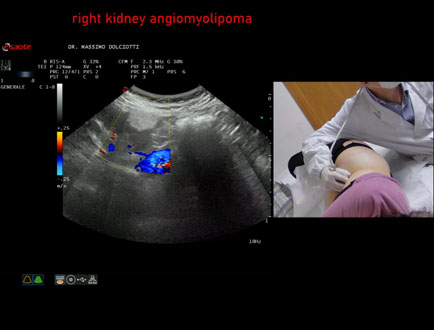

Data inserimento: 03/04/2026

Ecografia del: 12/03/2026

Strumento: Esaote MyLab Eight

Sonda: Convex Multifrequenza 1-8 MHz

Età Paziente: F 66 anni

Motivazione dell'esame: follow up per angiomiolipoma renale destro

Commento all'esame: le immagini ed il video documentano al rene destro, in sede corticale polo inferiore, immagine iperecogena, a margini definiti, delle dimensioni di 25 x 23 mm, senza segni di vascolarizzazione, da ricondurre, come prima ipotesi, ad angiomiolipoma.

Conclusioni: angiomiolipoma del rene destro (angiomyolipoma of the right kidney).

In collaborazione: Dr.ssa Marica Manfredi - Ancona, Dr. Ilir Qose - Ancona

Presentazione: Dr. Massimo Dolciotti - Ancona

Elaborazione digitale: Andrea Dini - Ancona